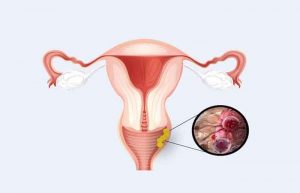

سرطان واژن چیست و چگونه درمان می شود؟ + علت و علائم